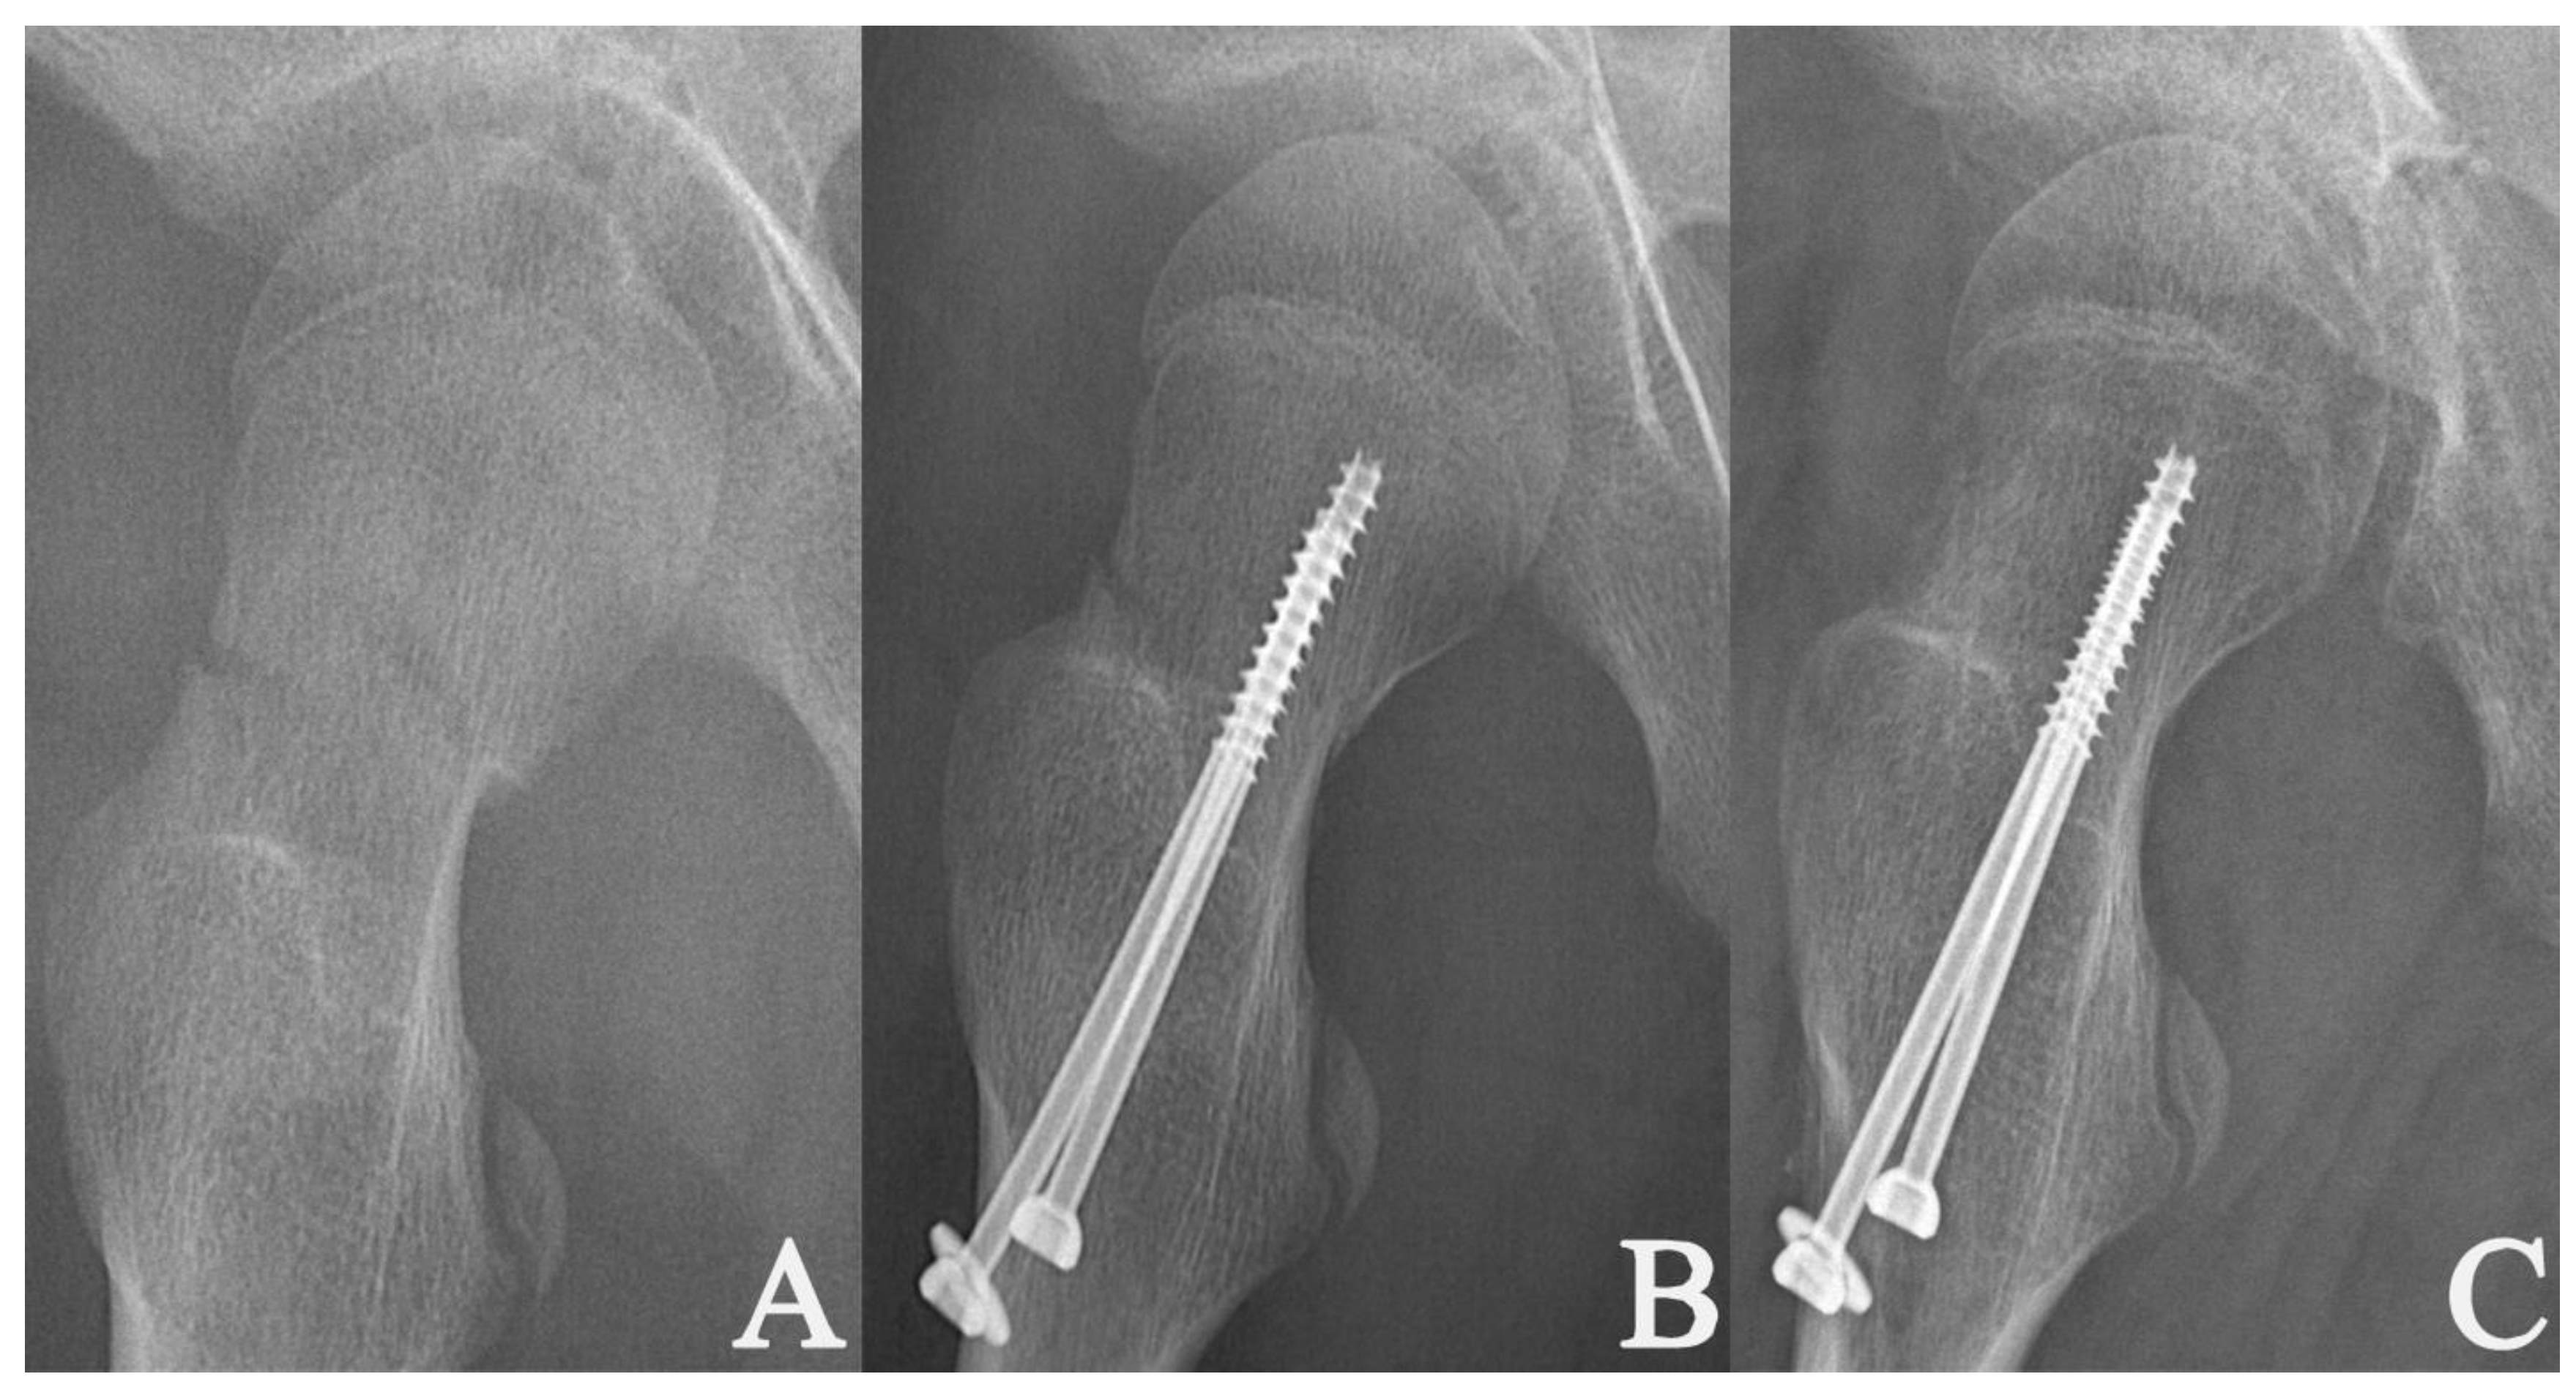

| Fixation method | Two cannulated screws (n = 100; 75.8%) | 3.1 ± 1.6 | 0.919 | 0.360 |

| Three cannulated screws (n = 32; 24.2%) | 3.4 ± 1.5 | |||